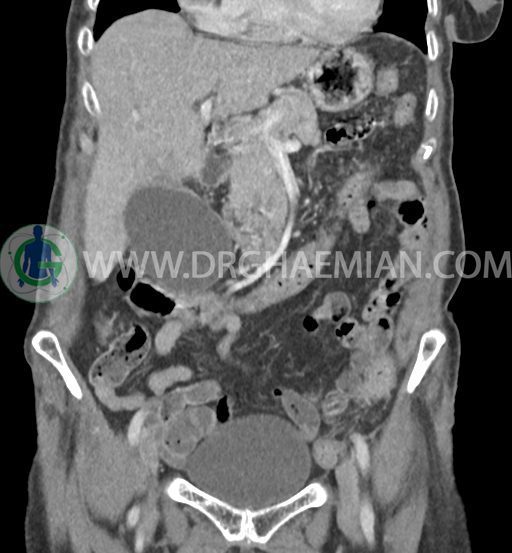

سی تی اسکن شکم و لگن با استفاده از اشعات ایکس تصاویر عرضی از ناحیه شکم و لگن ایجاد میکند. در این کیس سرطان مجرای صفراوی (کولانژیوکارسینوما)، توده در کبد، کیست کورتیکال در کلیه چپ، کلسیفیکاسیون دیواره آئورت و … دیده می شود.

در سی تی اسکن اسپیرال شکم و لگن با و بدون کنتراست خوراکی و وریدی (مولتی دیدکتور 16 با مقاطع ظریف و بازسازی های ساژیتال و کرونال) :

تصویر توده اندکی هیپودنس (HU=40 ) به ابعاد 30x40mm در سگمان 4b کبد ، با حدود ناواضح با enhancement هتروژن و قابل توجه پس از تزریق کنتراست ( HU=70 )، با شواهد تهاجم به گردن کیسه صفرا

کیسه صفرای دیلاته حاوی اسلاژ و سنگ های فراوان به قطر 5mm تا 10mm مطرح کننده کولانژیوکارسینوما

دیلاتاسیون خفیف مجاری صفراوی داخل کبدی

هرنی ونترال در ناحیه اپیگاستر حاوی چربی